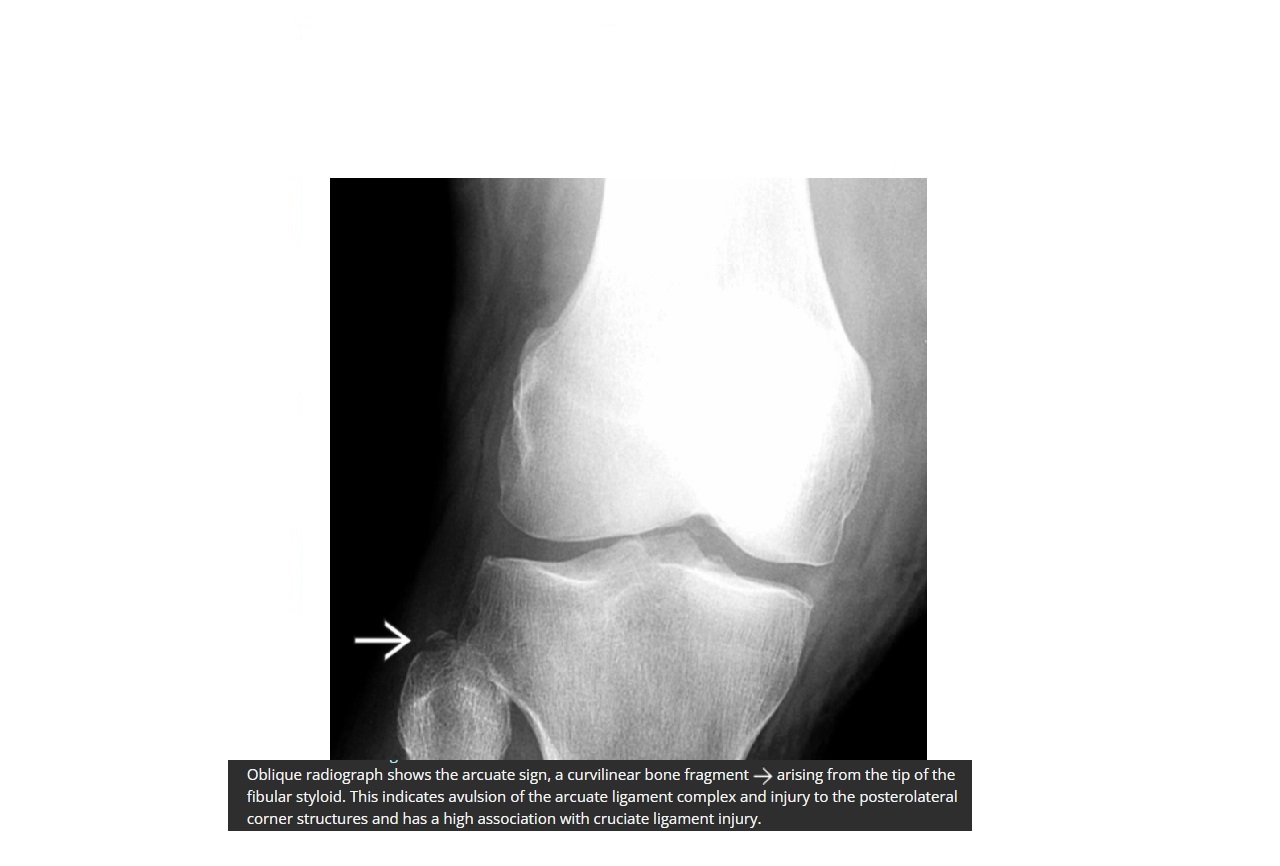

Arcuate sign ?

A

Avulsion of the proximal fibula

Associated with PCL tear